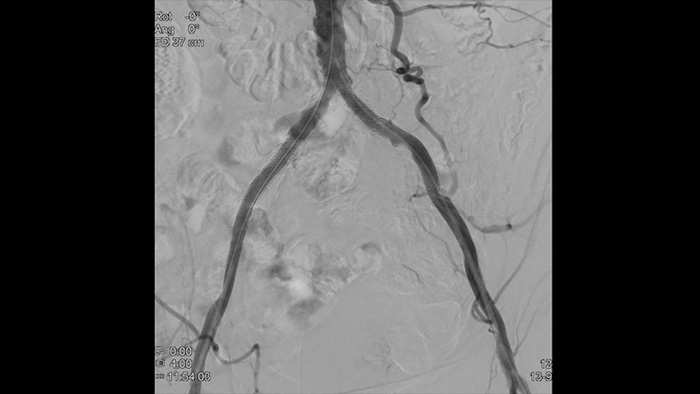

Nossos cateteres de diagnóstico por imagem periférico ajudam a avaliar o local da doença e a morfologia da lesão, incluindo cálcio e trombo. O IVUS também pode ser usado para dimensionar stents adequadamente e confirmar a completude do tratamento.

Imagens de vasos de alta definição com detalhes vasculares de qualidade superior, como apoio a estratégias precisas de tratamento, navegação e acompanhamento.